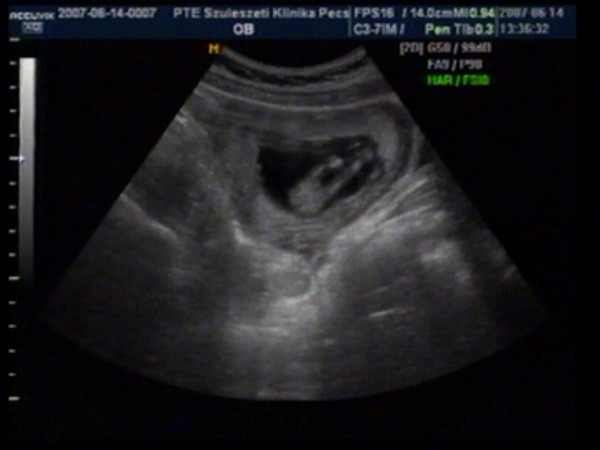

UH-s képeink..

Kép Kép

Júúúúúúúj, de cuki!!!!! És gratula a betöltött 12 héthez!